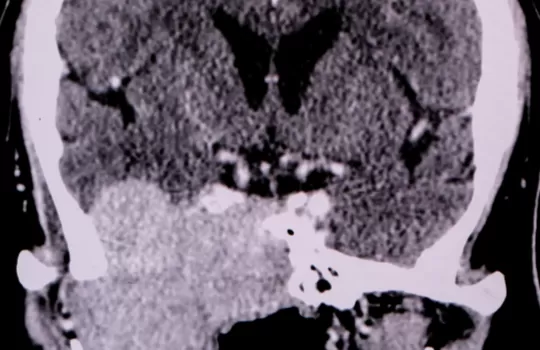

Burnunuzdaki şekil bozukluklarından nefes alma problemlerine, sinüzitten horlama şikayetlerinize, koku alamamadan geniz eti büyümesine kadar sorununuza özel yaklaşımlarla hem estetik kaygılarınızı ortadan kaldırıyor hem de sağlığınıza kavuşmanıza destek oluyoruz!